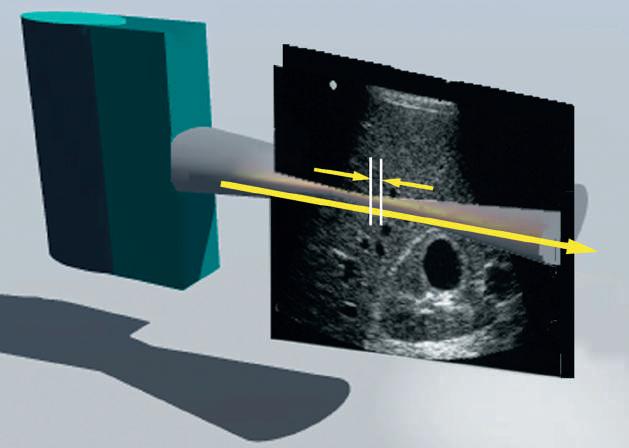

Ultrasound-based elastography permits study of the elastic behavior of tissue through two general approaches (Fig. 1.22): strain elastography and shear wave elastography.

Shear Wave Elastography

Longitudinal tissue compression results in the generation of transverse shear waves12,13 (see Fig. 1.22B). In shear wave elastography, shear waves are generated by repetitive compression produced by high-intensity pulses from the ultrasound transducer (see Fig. 1.22B). In contrast to longitudinal compressional waves that propagate very quickly in the human body (≈1540 m/sec), shear waves propagate slowly (≈1-50 m/sec). Shear waves are tracked with high frame rate images to determine their velocity. The propagation velocity of shear waves is directly proportional to Young modulus and provides a quantitative estimate of tissue stiffness14,15 (Fig. 1.24).

FIG. 1.22 Elastography. (A) Strain elastography (SE), and (B) shear wave elastography (SWE). Strain elastograms are images of tissue stiffness generated by analysis of speckle displacements before and after mechanical compression of tissue. The precompression frame is compared to a frame obtained after compression. In this example, the lesion is compressed much less than the surrounding tissue, indicating relative stiffness. SE is not quantitative and indicates only the relative hardness or softness of lesions compared to their surroundings. In SWE (B) high-intensity compression pulses from the transducer are focused on an area of interest, resulting in the generation of low-frequency shear waves. Speckle displacement resulting from shear (transverse) waves is tracked with multiple imaging frames in order to estimate shear wave velocity. Shear wave velocity is directly related to Young modulus, permitting a quantitative estimate of tissue stiffness.